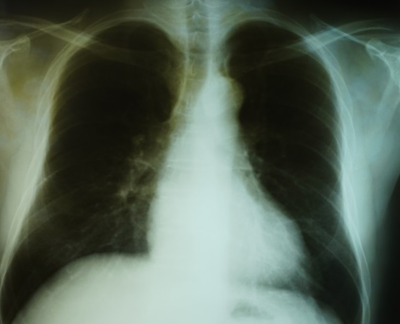

写真3 ボイラー工66歳初診時エックス線所見(ー)